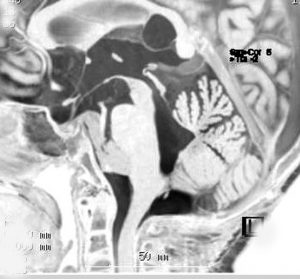

第4脳室上衣腫(良性と言える思春期例:EPN-PFB)

青年に発生したものです。かなり分化度の高い延髄背側 ovex 発生の上衣腫です。境界が明瞭なのですが,実際に側方(延髄小脳脚槽)で椎骨動脈や後下小脳動脈,下位脳神経に癒着しているので剥離は必ずしも容易ではありません。この例では幸い全摘出できました。